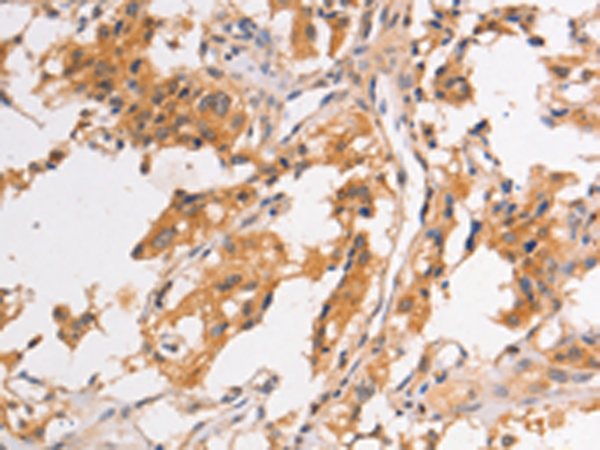

分类: 科研抗体货号: P07952别名: BARK2; ADRBK2应用: IHC反应种属: Human, Rat